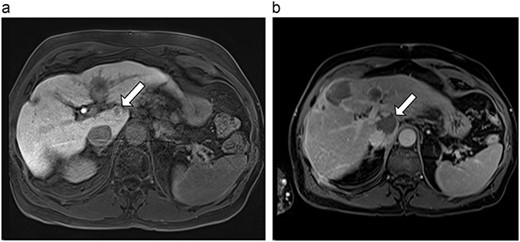

(a) Pre-ablation MRI demonstrates 6 mm lesion in caudate lobe of liver. (b) Post-ablation MRI (18 days postoperatively) demonstrates 40.4 mm complete ablation site in caudate lobe of liver.

| 1 (3a,b) | 61, F | Colon adenocarcinoma | 6-month FOLFOX | 1 | Laparoscopic microwave ablation | 6 | 40.4 | 34.4 | 10 | No |